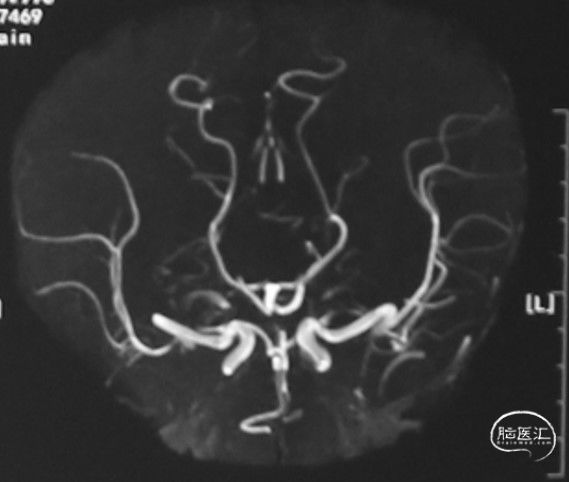

MRA:双侧大脑中动脉、左侧大脑前动脉重度狭窄至闭塞

左侧颈内动脉末段、大脑前动脉A1段、大脑中动脉M1段变细: